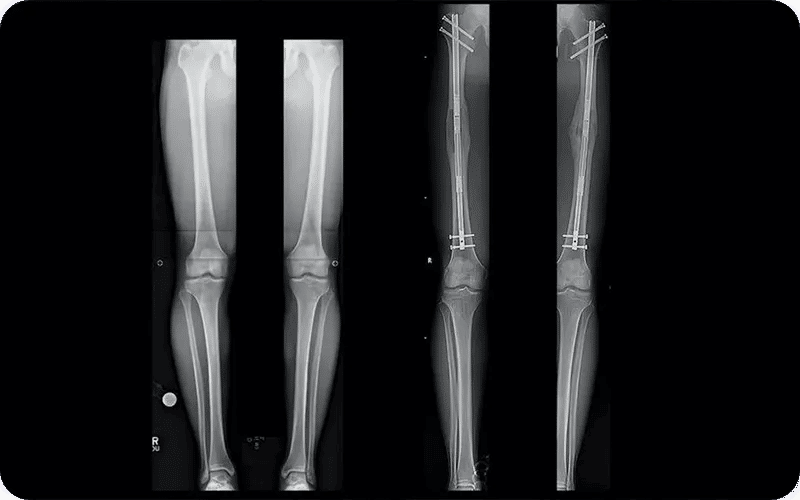

Surgery to Get Taller Before and After

Considering plastic surgery to get taller, people get this procedure to achieve specific beauty criteria. The before and after results of surgery to get taller are usually quite striking. After completing the recovery period of a leg surgery to get taller, patients notice a more elongated leg shape and a natural increase in overall height.

On average, femur surgery to get taller adds around 3 to 5 inches (7–12 cm). If both the tibia and femur are lengthened, the total height gain can reach up to 15 cm (about 6 inches). These changes create a permanent difference that is visible not only in height but also in body proportions, giving a more balanced and taller appearance.

Before and after photos show dramatic changes in height, but also highlight the significant surgical intervention and ongoing need for support and rehabilitation devices.